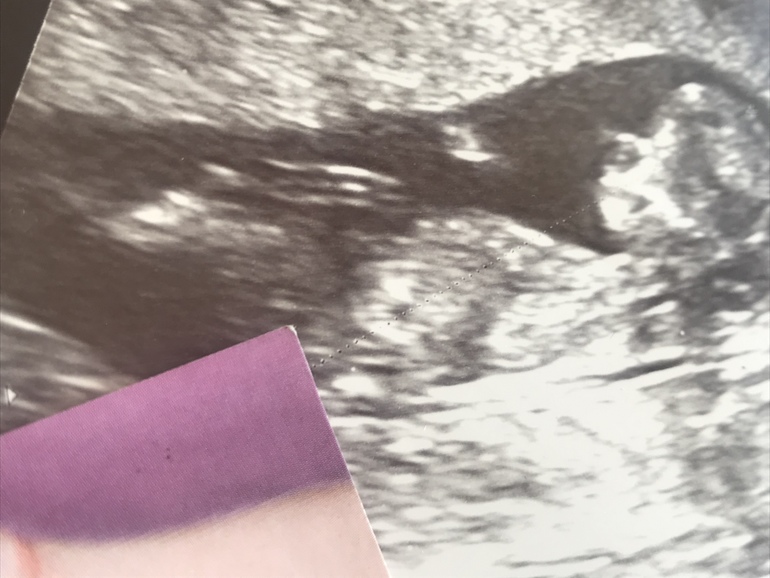

Определить пол )

Вопросы про УЗИ, обследования и анализы: что, где, как, когда?Вышла с долгожданного первого скрининга )

Все хорошо , пупс шевелится и кувыркается 😍

Узист сказала пол определять не умеет .

Но показала половой бугорочек ( смотрел ровно прямо. )

Может быть кто то в этом разбирается ?

На фото уголок листа показывает на полосочку светлую ( узист показывало это как половой бугорок .

Узист, когда спросила про пол , она приблизила это место . Такая палочка была и смотрела так же как на фото .

Поэтому как посмотрела на фото , сразу увидела то же место )

Девочка , потому что две полосочки , как кофейное зёрнышко ...

вот девочка в 16 недель , тоже кофейное зёрнышко чётко видно было ...